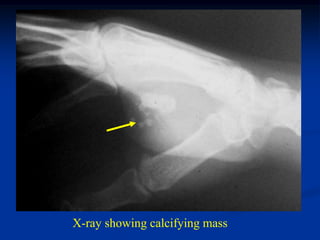

Case #293

36 year female

hemangioma hand

X-ray showing calcifying mass

AP and oblique views

Surgical removal

Case #293 36 yearfemale hemangioma hand

• 277.